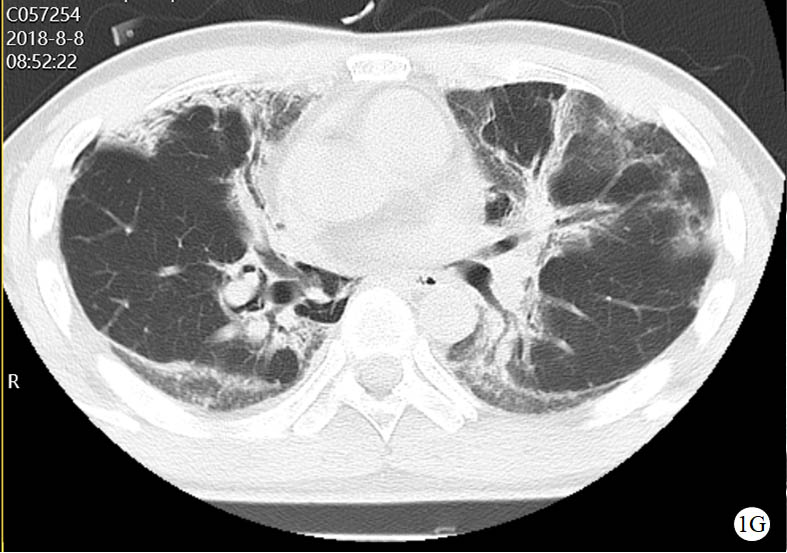

图 1 患者口服百草枯后胸部CT影像学变化

2018-08-08 CT图